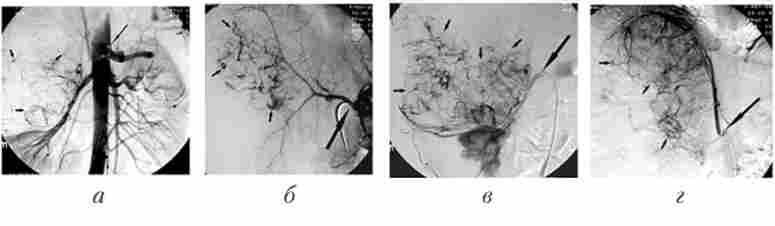

Селективні ангіограми правої зовнішньої сонної артерії до і після емболізації гілок верхньощелепної артерії гемостатичної губкою у хворого з носовою кровотечею

Мал. 29.7. Селективні ангіограми правої зовнішньої сонної артерії до і після емболізації гілок верхньощелепної артерії гемостатичної губкою у хворого з носовою кровотечею:

а, б - перед емболізація в бічній (А) і прямий (Б) проекціях визначаються ділянки гіперваскулярізація в проекції носової порожнини (стрілки); в - мікрокатетер встановлений в клиновидно-піднебінну частину верхньощелепної артерії (стрілка); г - контрольна ангіограма після емболізації: васкуляризация в проекції носової порожнини відсутній (стрілки)